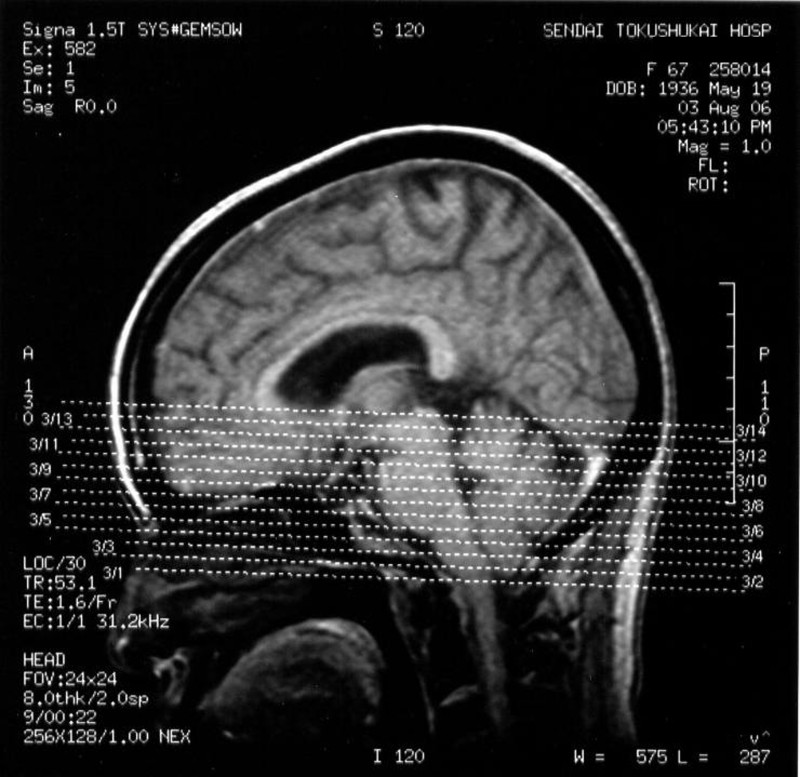

アーノルド・キアリを疑い、徳洲会病院放射線科にて脳幹を中心に画像診断を行ったが、異常なしとの回答(図6、7)。

図6

図7